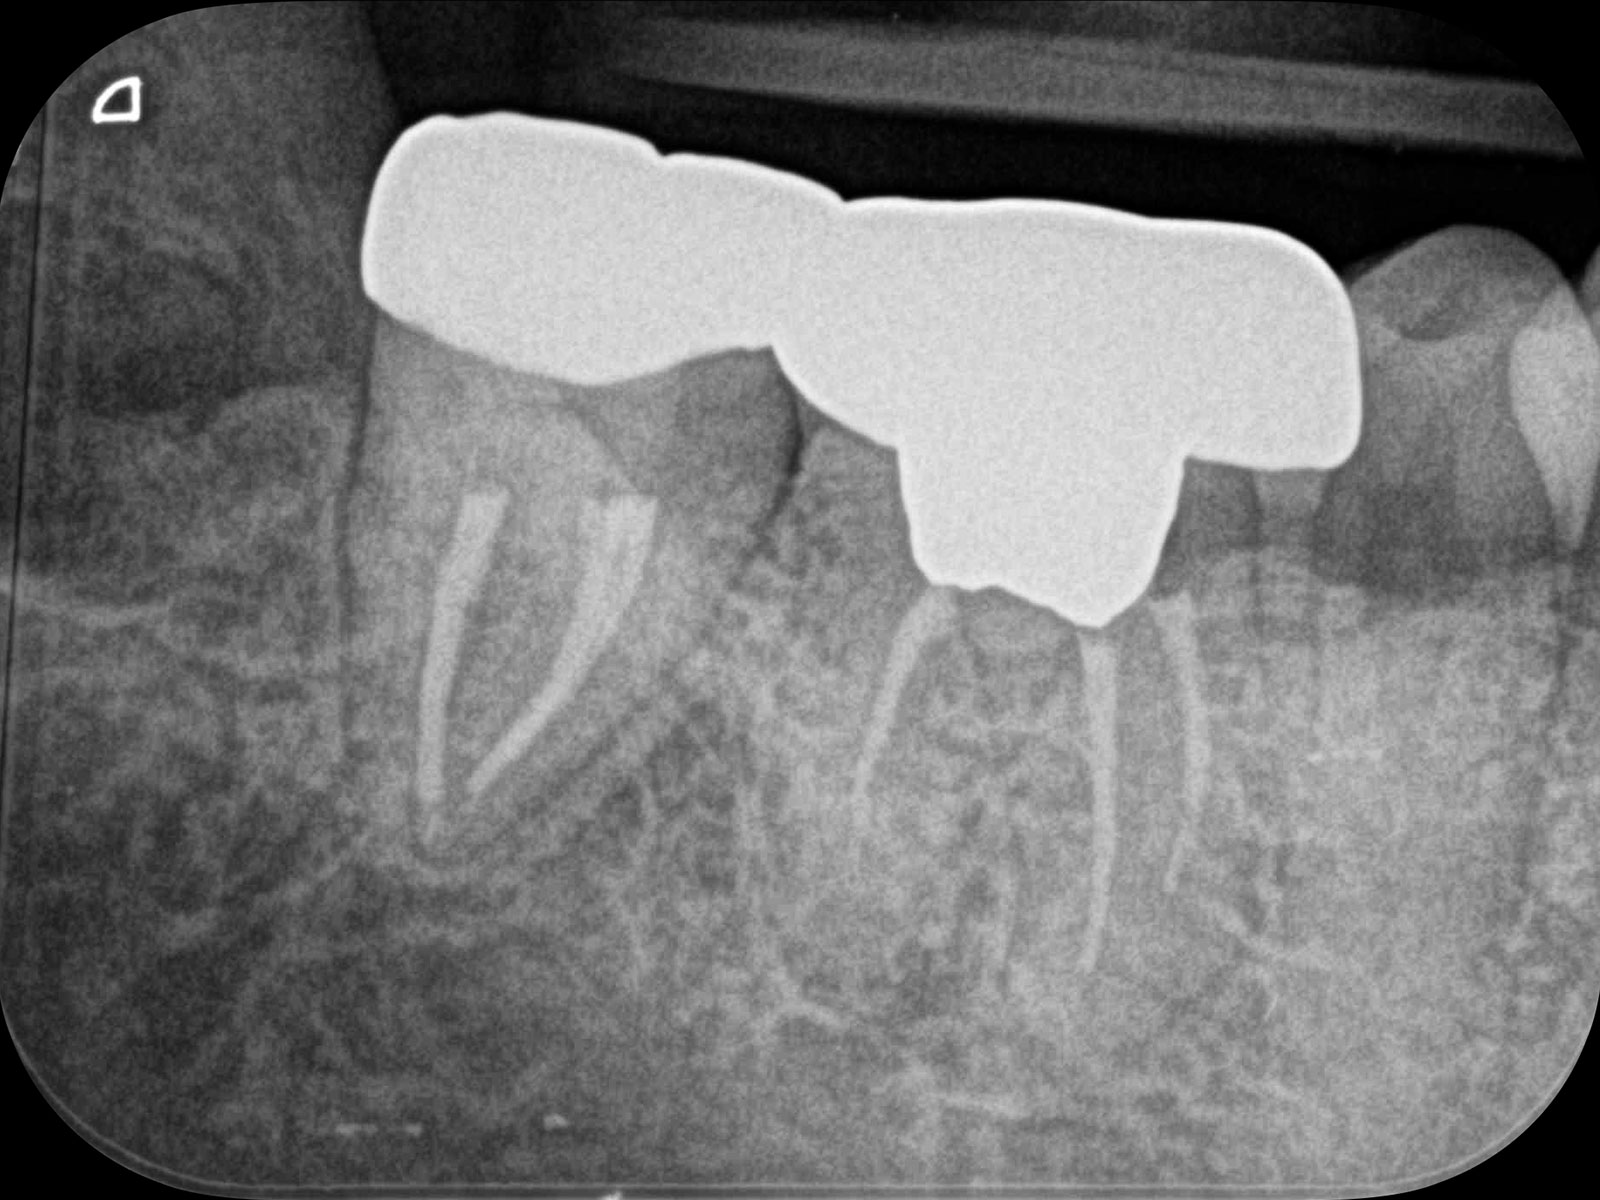

主訴: 噛むと痛い、奥歯が違和感ある

保険治療では発見することが難しい4つ目の神経を

歯を大きく削らずに見つけられます。